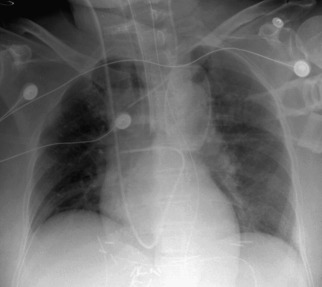

Complications of intubation ( Figs. 25-1 to 25-10 ) and ventilation that are apparent on a chest radiograph are often potentially life-threatening and should be excluded on every radiograph, both immediately following intubation and with each subsequent radiograph. These possibilities are listed in the following sections.